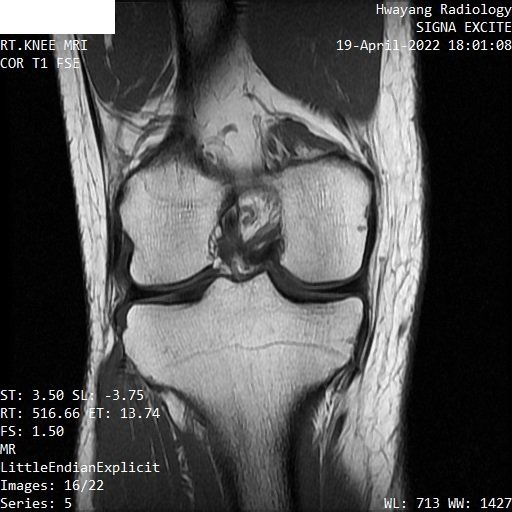

무릎연골 파열 mri좀 봐주세요 파열이 맞는지 궁금합니다.

오른쪽 무릎이 아파서 mri 찍어봤는데 집근처 병원에서 연골파열이라고 하는데

MRI 컷을 위와 같이 배열해놓은 것으로는 명확한 감별이 어렵습니다.

다만 연골부위의 MRI 상 이상 소견이 있는 것은 사실입니다.